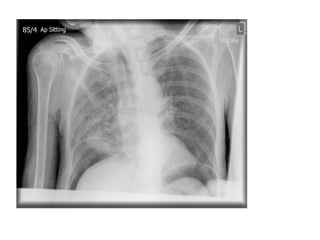

Acute abdominal pain in

an ICU patient, male, 65.

Bowel perforation

Clinical Features

•severe and generalised abdominal pain (upper)

•gradual and localised pain (lower)

•anorexia, nausea and vomiting

•rigid abdomen and generalised tenderness

•guarding and rebound

•bowel sounds range from quiet to absent

Aetiology

•gastric and duodenal ulceration

•infection (diverticulitis, appendicitis), ischaemia and cancer

•blunt and penetrating trauma

•ingestion of corrosive materials

•iatrogenic causes (ERCP, colonoscopy, laparotomy, biopsy)

• Rigler’s sign LUQ

• Free

intraperitoneal

gas is widespread

with moderate

dilatation of small

bowel in particular

and there may

also be intramural

gas.